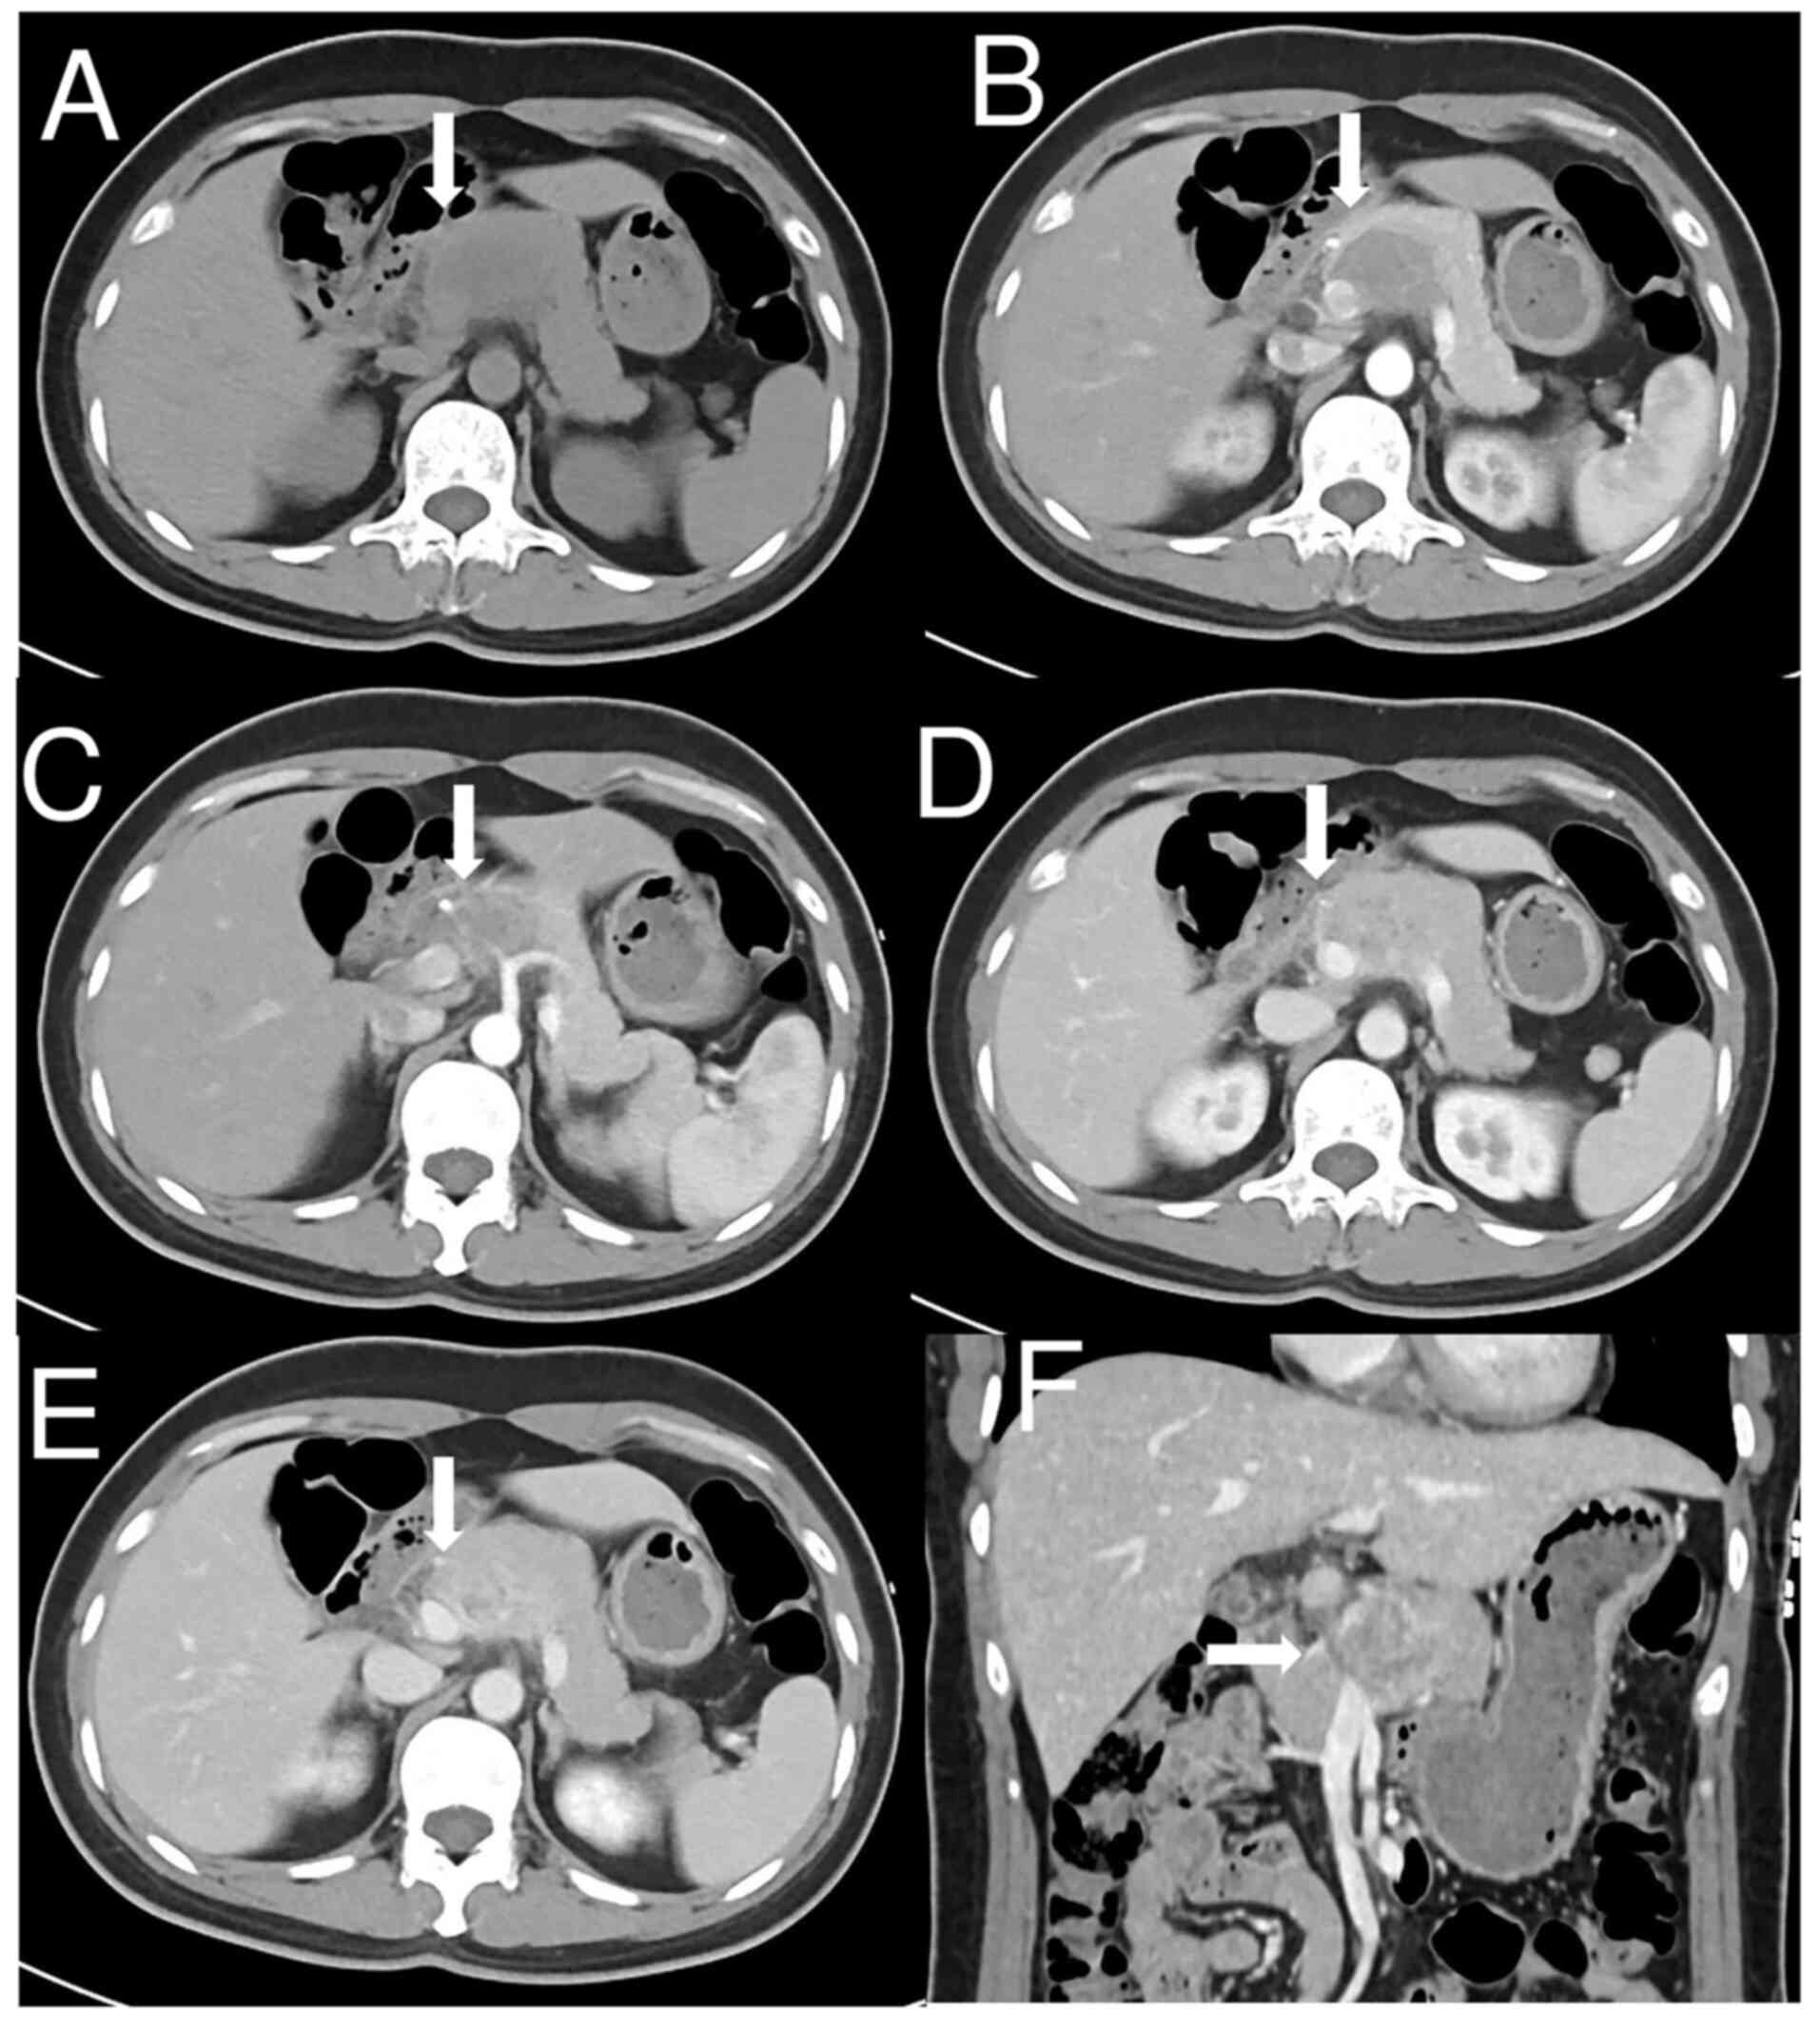

In May 2023, a 40-year-old female patient presented with a fever that had persisted for several days without accompanying symptoms to Sichuan Provincial People's Hospital (Chengdu, China) for treatment. The medical and family history of the patient were unremarkable, and the patient was in normal physical condition. All laboratory data, including tumor markers such as carcinoembryonic antigen (<1.73 ng/ml; normal range, ≤5 ng/ml) and carbohydrate antigen 19-9 (10.97 U/ml; normal range, ≤43 U/ml) were within normal limits. Abdominal CT (Fig. 1A) demonstrated a solid mass measuring 2.4×4.5 cm located in the pancreatic head and body. The tumor was heterogeneous and lacked a fat component. Dynamic contrast-enhanced CT demonstrated slightly heterogeneous enhancement in the arterial phase (Fig. 1B), moderate enhancement in the venous phase (Fig. 1D) and persistent enhancement in the delayed phase (Fig. 1E), with encapsulation of the common hepatic artery, splenic vein and portal vein (Fig. 1C and F). No lymphadenopathy was observed.

Figure 1.

Radiological findings. (A) Unenhanced axial CT image revealing a heterogenous mass in the pancreatic head and body (arrow). (B) Arterial phase axial CT image showing slight enhancement of the lesion (arrow). (C) Arterial phase axial CT image showing the tumor invaded the common hepatic artery(arrow). (D) Venous phase axial CT image indicating further uneven enhancement of the lesion with invasion to the splenic vein (arrow). (E) Delayed phase axial CT image showing persistent enhancement of the lesion (arrow). (F) Delayed phase coronal CT image showing heterogenous enhancement of the lesion with invasion to the portal vein (arrow).